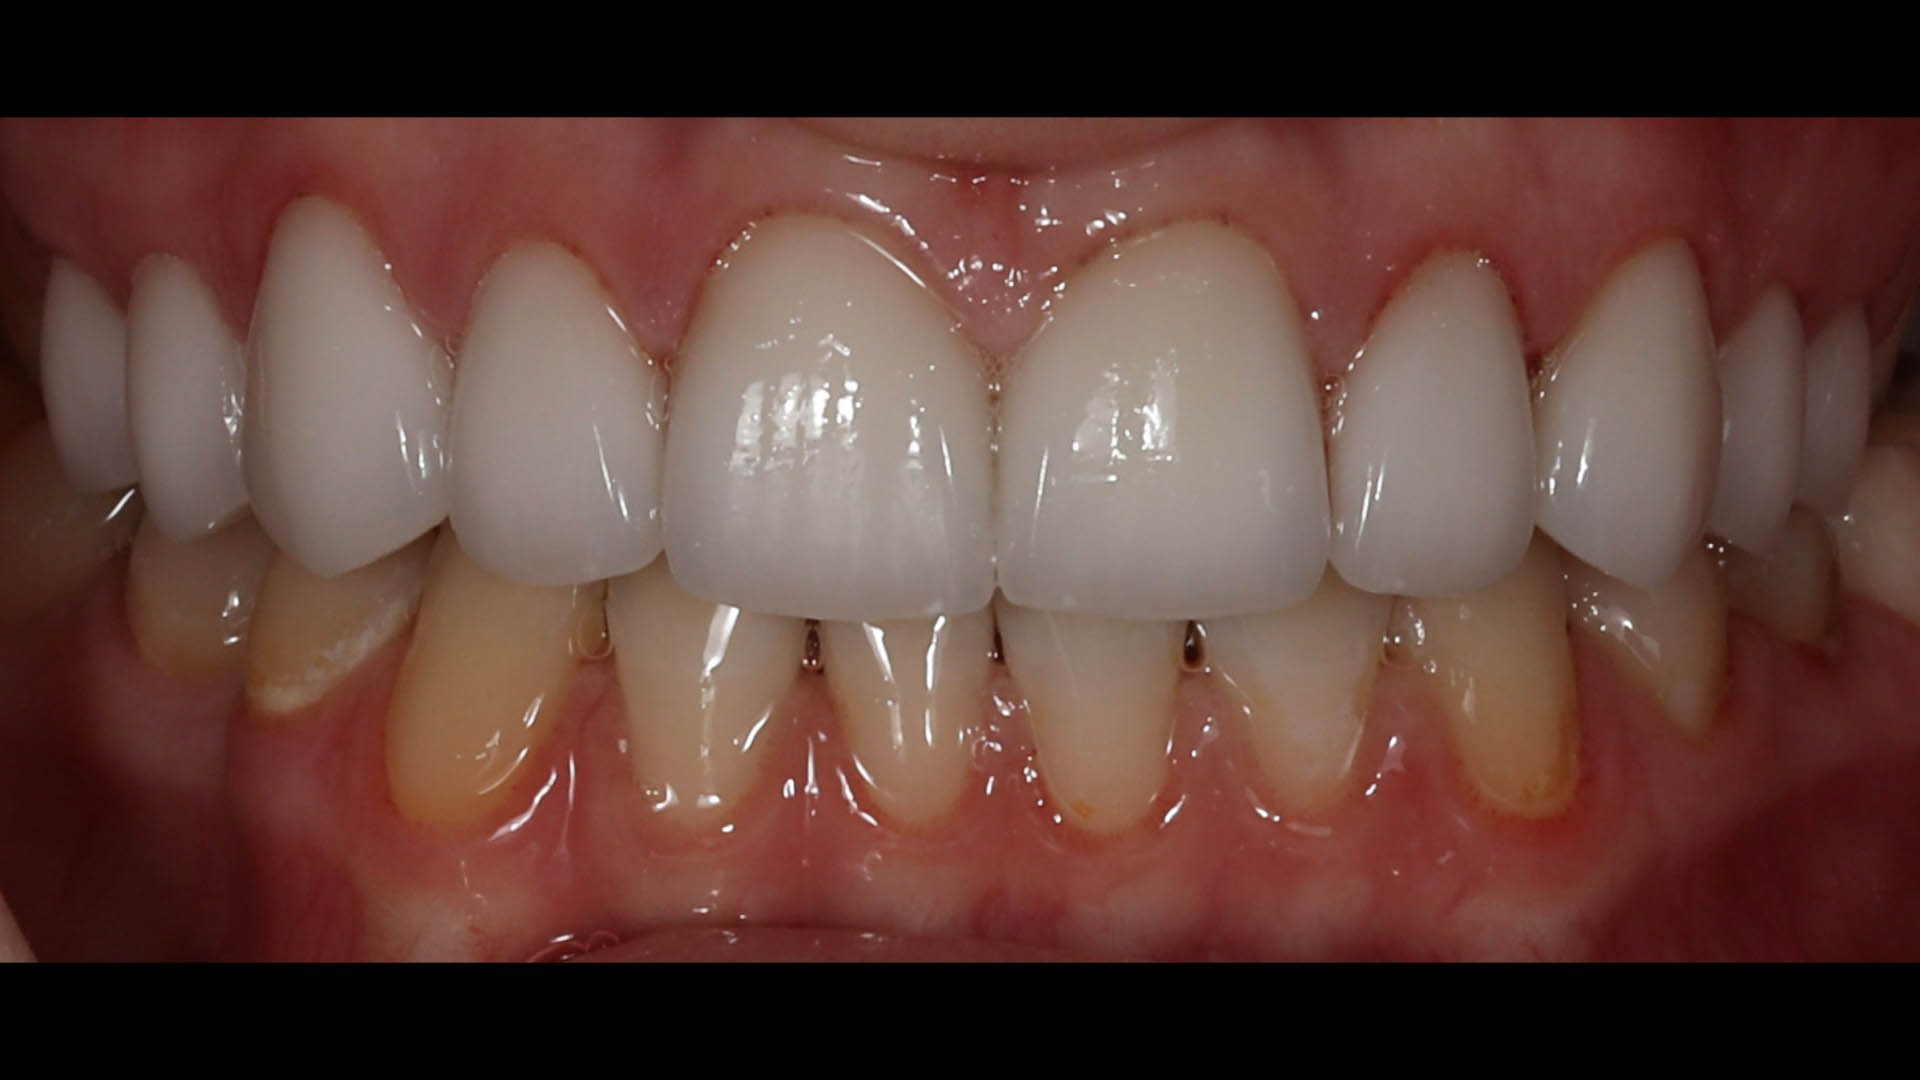

Take a glimpse into the magic of Coral Gables Dentistry through our before and after pictures. See firsthand the incredible smile makeover transformations that have brought confidence and joy to our patients.